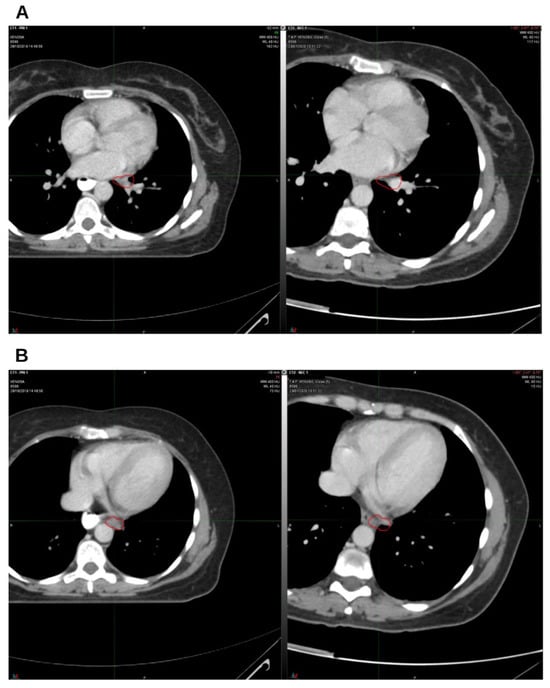

Integrative Use of Cannabidiol, Melatonin, and Oxygen–Ozone Therapy in Triple-Negative Breast Cancer with Lung and Mediastinal Metastases. A Case Report

Background and Clinical Significance: Breast cancer is the most frequent malignancy in women. Metastatic breast cancer is considered a treatable but incurable condition, with a median overall survival of only 2–3 years. Among its subtypes, triple-negative breast cancer (TNBC) accounts for a high proportion of breast cancer-related deaths. It is characterized by an aggressive clinical course, early recurrence, and a strong propensity for visceral and brain metastases. Case Presentation: We report the case of a Caucasian woman who developed systemic disease recurrence with lung and mediastinal lymph node metastases, occurring two years after her primary diagnosis and treatment for TNBC. The patient received three months of chemotherapy combined with an adjuvant integrative protocol consisting of melatonin, cannabidiol, and oxygen–ozone therapy. This combined approach led to the complete disappearance of the lung nodules. Subsequently, stereotactic radiotherapy was performed and, in association with the ongoing integrative treatment, resulted in a significant reduction in mediastinal adenopathy. Introduction of immunotherapy, supported continuously by the same adjuvant strategy, achieved a complete and durable remission. Strikingly, the patient remained disease-free five years after the diagnosis of lung and mediastinal metastases. Conclusions: This clinical case highlights the potential benefit of using melatonin, cannabidiol, and oxygen–ozone therapy as part of an integrative approach in patients with aggressive metastatic TNBC. While it is not possible to establish causality from a single case, the sustained remission observed suggests that such unconventional adjuvant strategies could play a supportive role in enhancing the efficacy of standard oncologic therapies. Full article

Figure 1